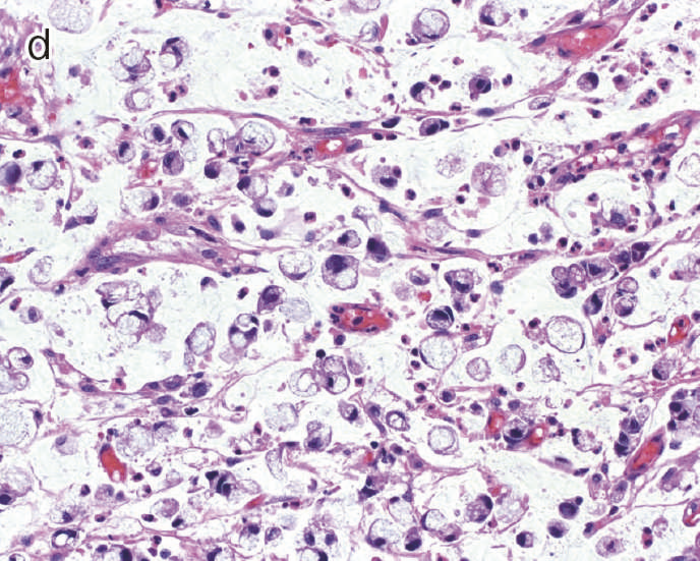

- 肉眼的特徴

通常の散発性進行大腸癌の多くは潰瘍限局型(2型)であるが,UC関連進行大腸癌は潰瘍浸潤型(3型),びまん浸潤型(4型)や分類不能型(5型)が多いとされる(図7)。初期病変であるdysplasiaの肉眼形態に関しては,混合型を含む約70%の症例が何らかの隆起成分を有することが報告されている1,2)。ただ同じ隆起といっても,UC関連大腸腫瘍の多くは境界不明瞭な丈の低い顆粒状・結節状・不整扁平隆起を呈する一方で,散発性腫瘍は有茎性もしくは亜有茎性病変,境界や立ち上がりが明瞭な病変であることが多く,詳細な肉眼形態の観察は両者の鑑別に重要である。二番目に多い肉眼形態は平坦型であり,全体の約30%を占める1,2)。散発性大腸腫瘍の平坦型は極めて頻度が低いことから,平坦型成分の存在もdysplasiaの特徴といえる(図8)。

図7 UC関連進行大腸癌の代表的な肉眼像

- 内腔狭窄を伴った5型の腫瘍(矢印)を認める。

- 組織学的には,粘液癌あるいは低分化腺癌が壁内に浸潤している像を認める。

- 組織学的特徴

dysplasiaはその異型度によりLGDとHGDに二分される(図9)。LGDは基本的に核の極性が比較的保たれており,表層への分化傾向がみられることを特徴とし,しばしば反応性異型との鑑別を要する。多彩な形態像を示すこともdysplasiaの特徴である。味岡らは,UC関連大腸腫瘍を5つの特殊なパターン(表層分化を示す分化型腺癌,分化細胞を豊富にもつ分化型腺癌,分化細胞に乏しい分化型腺癌,未分化型腺癌または分化型腺癌の脱分化,癌の判定が困難な分化型腫瘍)に分類し報告している3)。2019年に出版されたWHO分類には,IBDを背景に発生する粘膜内腫瘍をInflammatory bowel disease-associated dysplasia of the colorectumと呼称し,組織形態に基づき,intestinal(adenomatous)subtype,serrated subtype,mucinous type,a subtype with eosinophilic cytoplasm and marked goblet cell depletion,crypt cell subtypeやこれらの組織像が混在したmixed subtypeなどが存在すると記載されている4)(図10)。

このように多彩な像を呈するdysplasiaでは,特に異型度が低い場合に反応性異型との鑑別にしばしば難渋するが,dystrophic goblet cell,endocrine cell hyperplasia,Paneth細胞化生などの特徴的な上皮細胞分化異常を示す特殊な異型上皮の存在が形態学的な鑑別として有用である。また,dysplasiaでは,腫瘍発生早期の段階よりTP53遺伝子異常が起こることが知られている。したがって,上記の形態学的な異常とともに,免疫染色におけるp53蛋白異常発現の有無が反応性異型や散発性腺腫との鑑別において重要となる(TP53遺伝子変異が見られる際には,免疫染色においてp53蛋白過剰発現あるいは完全欠失を示すことが知られている)。これまでに,一般大腸腺腫・癌ではp53蛋白過剰発現はその異型度に相関するのに対し(腺腫で0.8~3.4%,低異型度癌で35.3%,高異型度癌で71.7%),dysplasiaでは低異型度の段階から高頻度(75%)にp53蛋白過剰発現を呈することが報告されている5)。したがって,特に低異型度腫瘍でp53蛋白異常発現パターンを示す場合はdysplasiaの可能性が高く,反応性異型との鑑別において診断的意義が高い。また,表層分化傾向を示すLGDではp53蛋白の過剰発現がある場合でも表層部ではp53蛋白の発現減弱がしばしば観察されるのに対し(unique basal patternと呼ばれる),HGDでは全層性にp53蛋白過剰発現を示すことが多い。Ki-67(増殖マーカー)染色では,dysplasiaでは細胞増殖帯が粘膜深層~中層に位置するが(bottom-up pattern),散発性腺腫では細胞増殖帯が腺管表層~中層に分布することが知られている(top-down pattern)。これらの免疫染色パターンは,dysplasiaと反応性異型や散発性腺腫との鑑別の際に重要な手がかりとなる(図9,図11)(CQ 12,CQ 13)。

図10 Dysplasiaの多様な組織像

- 表層分化を示すdysplasia。

- 分泌顆粒の局在が核上,核下,表層と不規則な分布を示すdystrophic goblet cellを含むdysplasia。

- UC関連粘膜内低分化腺癌:粘膜内において粘液癌あるいは印環細胞癌が認められる。

- cの拡大像。